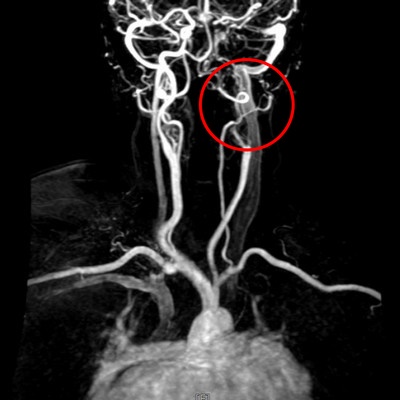

腦中風臨床表現包括平衡感、視力或手腳肌力下降,或是臉部或嘴角的歪斜、口齒不清等,甘女士的兒子因職業原因相當警覺,察覺到媽媽的症狀疑似腦中風,雖右手和右腳尚能行動,但握力明顯變差,因此果斷將病人送醫。救護車抵達急診後,醫療團隊立即為病人做電腦斷層檢查,排除出血型腦中風,並做核磁共振,發現左腦有明顯發亮區域,以及缺少了左側內頸動脈的顯影,即確認是左腦急性腦塞與左側內頸動脈完全阻塞。

急診隨即會診神經外科團隊做腦血管內取栓術,利用介入技術將阻塞腦部大血管的血塊取出,改善血流循環,降低腦組織受損的範圍,在病人抵達醫院90分鐘內就完成了取栓治療。取出血栓、打通大血管後,甘女士的意識及說話方式恢復清晰,右半身肌力也已恢復正常,能夠自如下床行動。她表示,很慶幸兒子發現症狀後當機立斷叫救護車,直接將她從花蓮南區送往花蓮慈院,也感恩醫療團隊二十四小時待命的高效率,不僅救回她一命,也沒有在腦部留下不可逆的神經損傷。